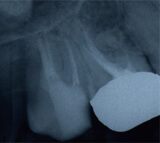

レントゲン写真により経過を確認します

黒い影は骨が溶け膿を持っている

黒い影が無くなり骨の再生が認められ経過は良好です